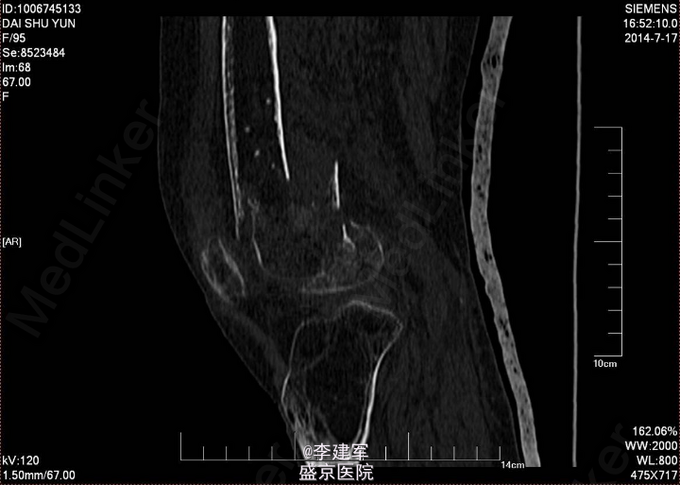

右股骨髁上粉碎性骨折 患者高龄,完善心电图,肺部CT,生化检查等,查无手术禁忌症。择期手术治疗。 手术拟行右股骨髁上粉碎性骨折闭合复位内固定术。 决定使用Liss钢板

患者高龄选用Liss钢板做闭合复位,减小手术创口。